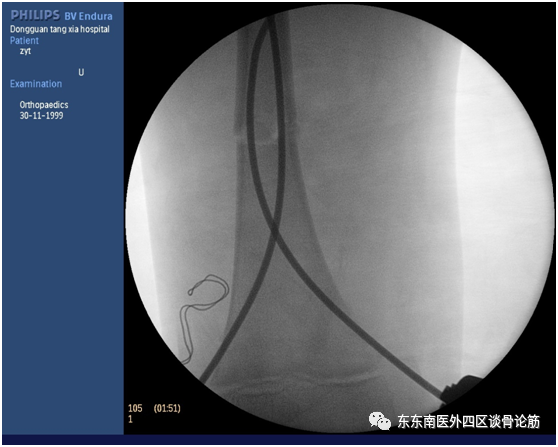

(C臂X光机引导下闭合复位穿针)

(术中透视)